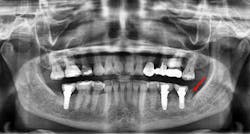

Late complications of bone augmentation are now recognized more frequently and include late resorption, foreign body reaction (figures 2a–2b), late breakdown of grafted sites (figures 3a–3e), lack of keratinized tissue and poor esthetics, as well as implant failure. While all bone augmentation procedures result in some degree of bone remodeling and resorption, significant late graft resorption can jeopardize the supporting bone around an already integrated implant, resulting in implant dehiscence, peri-implant disease, and late implant failure (figures 4a–4c). The degree of resorption depends on three important factors: alveolar defect configuration, patient factors, and the technique and grafting materials chosen.3

Figures 3a–3e: Socket preservation was performed at the site of the left mandibular second molar after extraction, using a biomaterial two years prior to implant placement. Six years after implant placement, sequestration of the biomaterial is seen, resulting in peri-implant infection and failure of the implant.